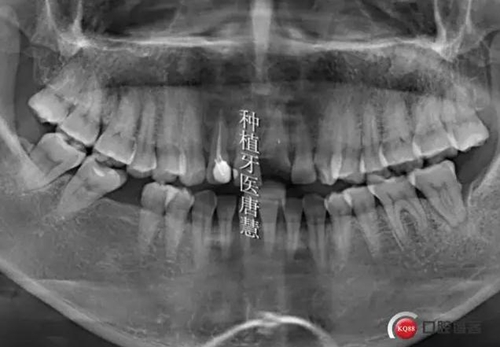

患者白XX,護士,上前牙數年前樁冠修復,一天前折斷,來診,要求不能有空牙期

查見21根折,上前牙2-2樹脂貼面修復,邊緣不密合,繼發(fā)齲,治療計劃:1、上前牙美學修復,DSD設計,21種植,臨時修復。2、21冠延長后樁冠修復,但美觀效果不理想

患者要求先解決21問題,種植修復

術前曲斷